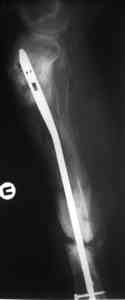

Имя     : 4.jpg

Тип     : image/jpeg

Размер  : 26242 байтов

Описание: отсутствует

Url     : http://weborto.net:8080/pipermail/ortho/attachments/20080516/529c86f2/attachment-0005.jpg